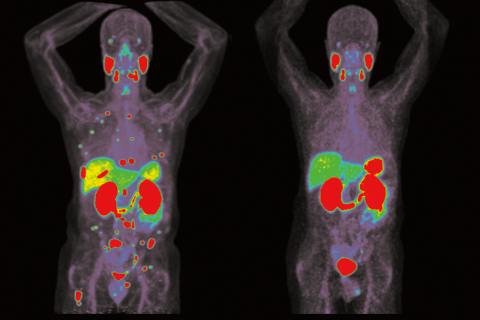

The focus of Czernin's research is to refine the clinical role of molecular PET imaging. He has adopted a translational research approach by which radioactive ligand uptake in cell cultures determines the use of specific molecular imaging probes in small animals and later on in humans.